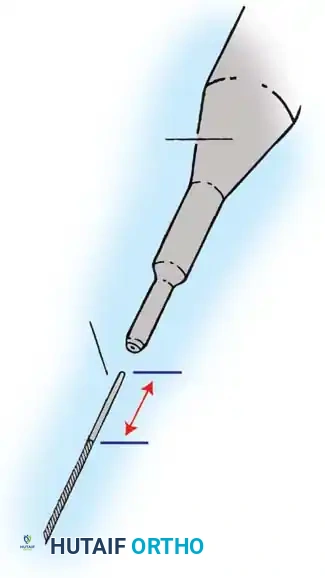

The Moe Technique (Lumbar Spine)

In the lumbar spine, the facet joints are oriented in a more sagittal plane, necessitating a modified approach.

Fig. 38-27: The Moe technique adapted for lumbar facet fusion, addressing the sagittal orientation of the joints.

- Utilize a small osteotome or a needle-nose rongeur to resect the adjoining joint surfaces.

- This creates a distinct rectangular defect within the sagittally oriented joint space.

- Pack this defect forcefully with cancellous bone graft.

- Proceed to decorticate the entire exposed posterior elements (laminae and transverse processes) using Cobb gouges, always directing force away from the spinal canal.